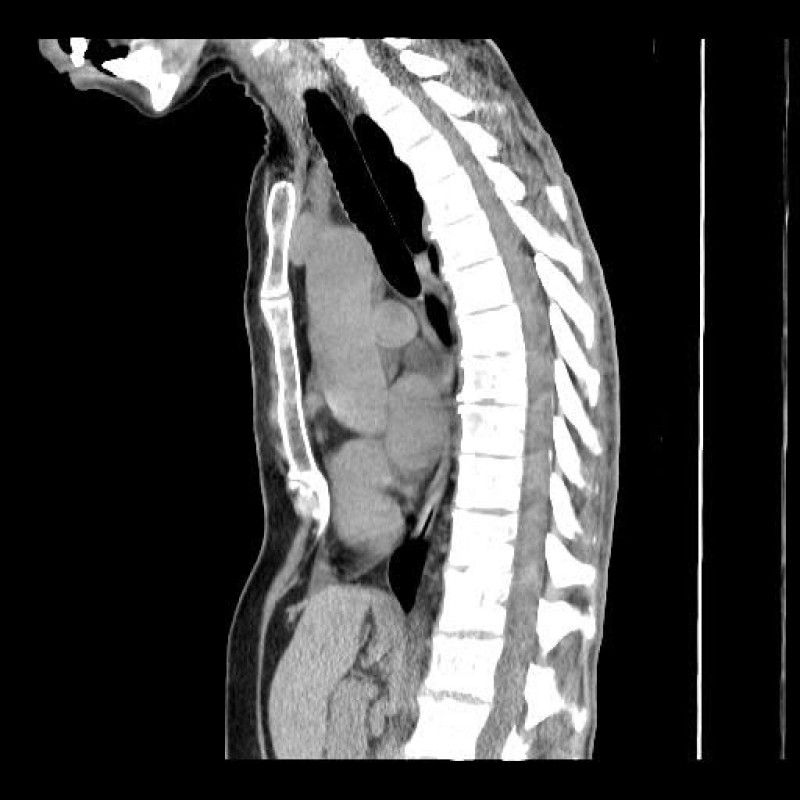

Hello. My name is Jennifer Aldridge and have recently found out that I will need surgery to give my heart and lungs more space. I am so scared. It will require me to be off 4-6 months from work as i have heavy lifting involved in my work. This surgery will allow me to breath as I should and heart compression released. My spine and sternum almost touch. I need to pay for some of surgery costs and living costs while im off from work. I have already exhausted all sick and annual leave and savings. Please help if you can. ❤️🙏